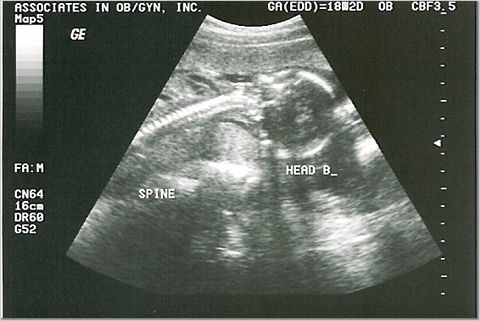

18 weeks - 7 & 8 ounces

We were supposed to find out the sexes, but they were too active for the tech to see!

Baby A and Baby B Spine